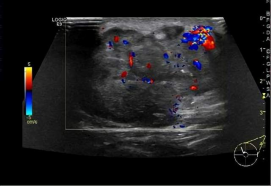

影像检查:乳腺彩超、乳腺X线、核磁共振。

乳腺彩超:首选检查。